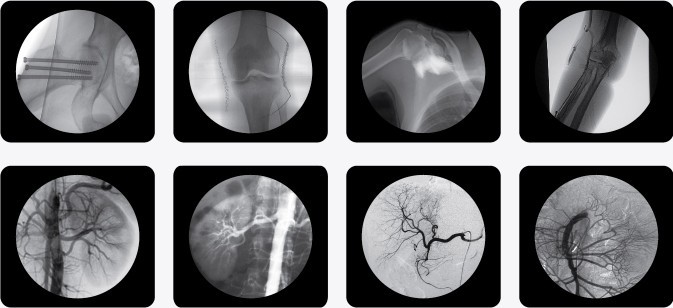

一、C型臂X光機PLX7000B的用途

廣泛應用于 介入科、骨科、外科、矯形外科、泌尿外科、脊柱外科、腹部外科、疼痛科、心臟科、消化科、婦科及手術室等。

三、C型臂X光機PLX7000B數字高清影像,支持您做出精確診斷

·數字化高頻發生器,采用微焦點,確保精準的射線劑量控制,滿足您的多種復雜臨床診治要求。

·球館大熱容設計,保證設備持久工作能力,伴隨您一同應對各種復雜手術。

·全數字化百萬像素影像采集系統,優化設計和配置,為您提供高分辨率、高灰階圖像,支持您做出精確診斷。

·專業的圖像處理系統,具備非凡處理能力,確保您的所想即您的所得

1、內置先進圖像自動優化處理、增強模塊,實時顯示自動優化后的清晰臨床影像。

2、專業的影像處理工作站具備窗寬窗位調節、自動伽瑪校正、興趣點、反相、降噪、平滑、銳化等豐富且強大影像處理功能,帶給您更強大的診斷信心。

·專用高清醫用液晶顯示系統,呈獻給您高亮度、高對比度的臨床圖像;對比自然,有益于診斷的圖像細節顯示更加清晰、層次更加豐富